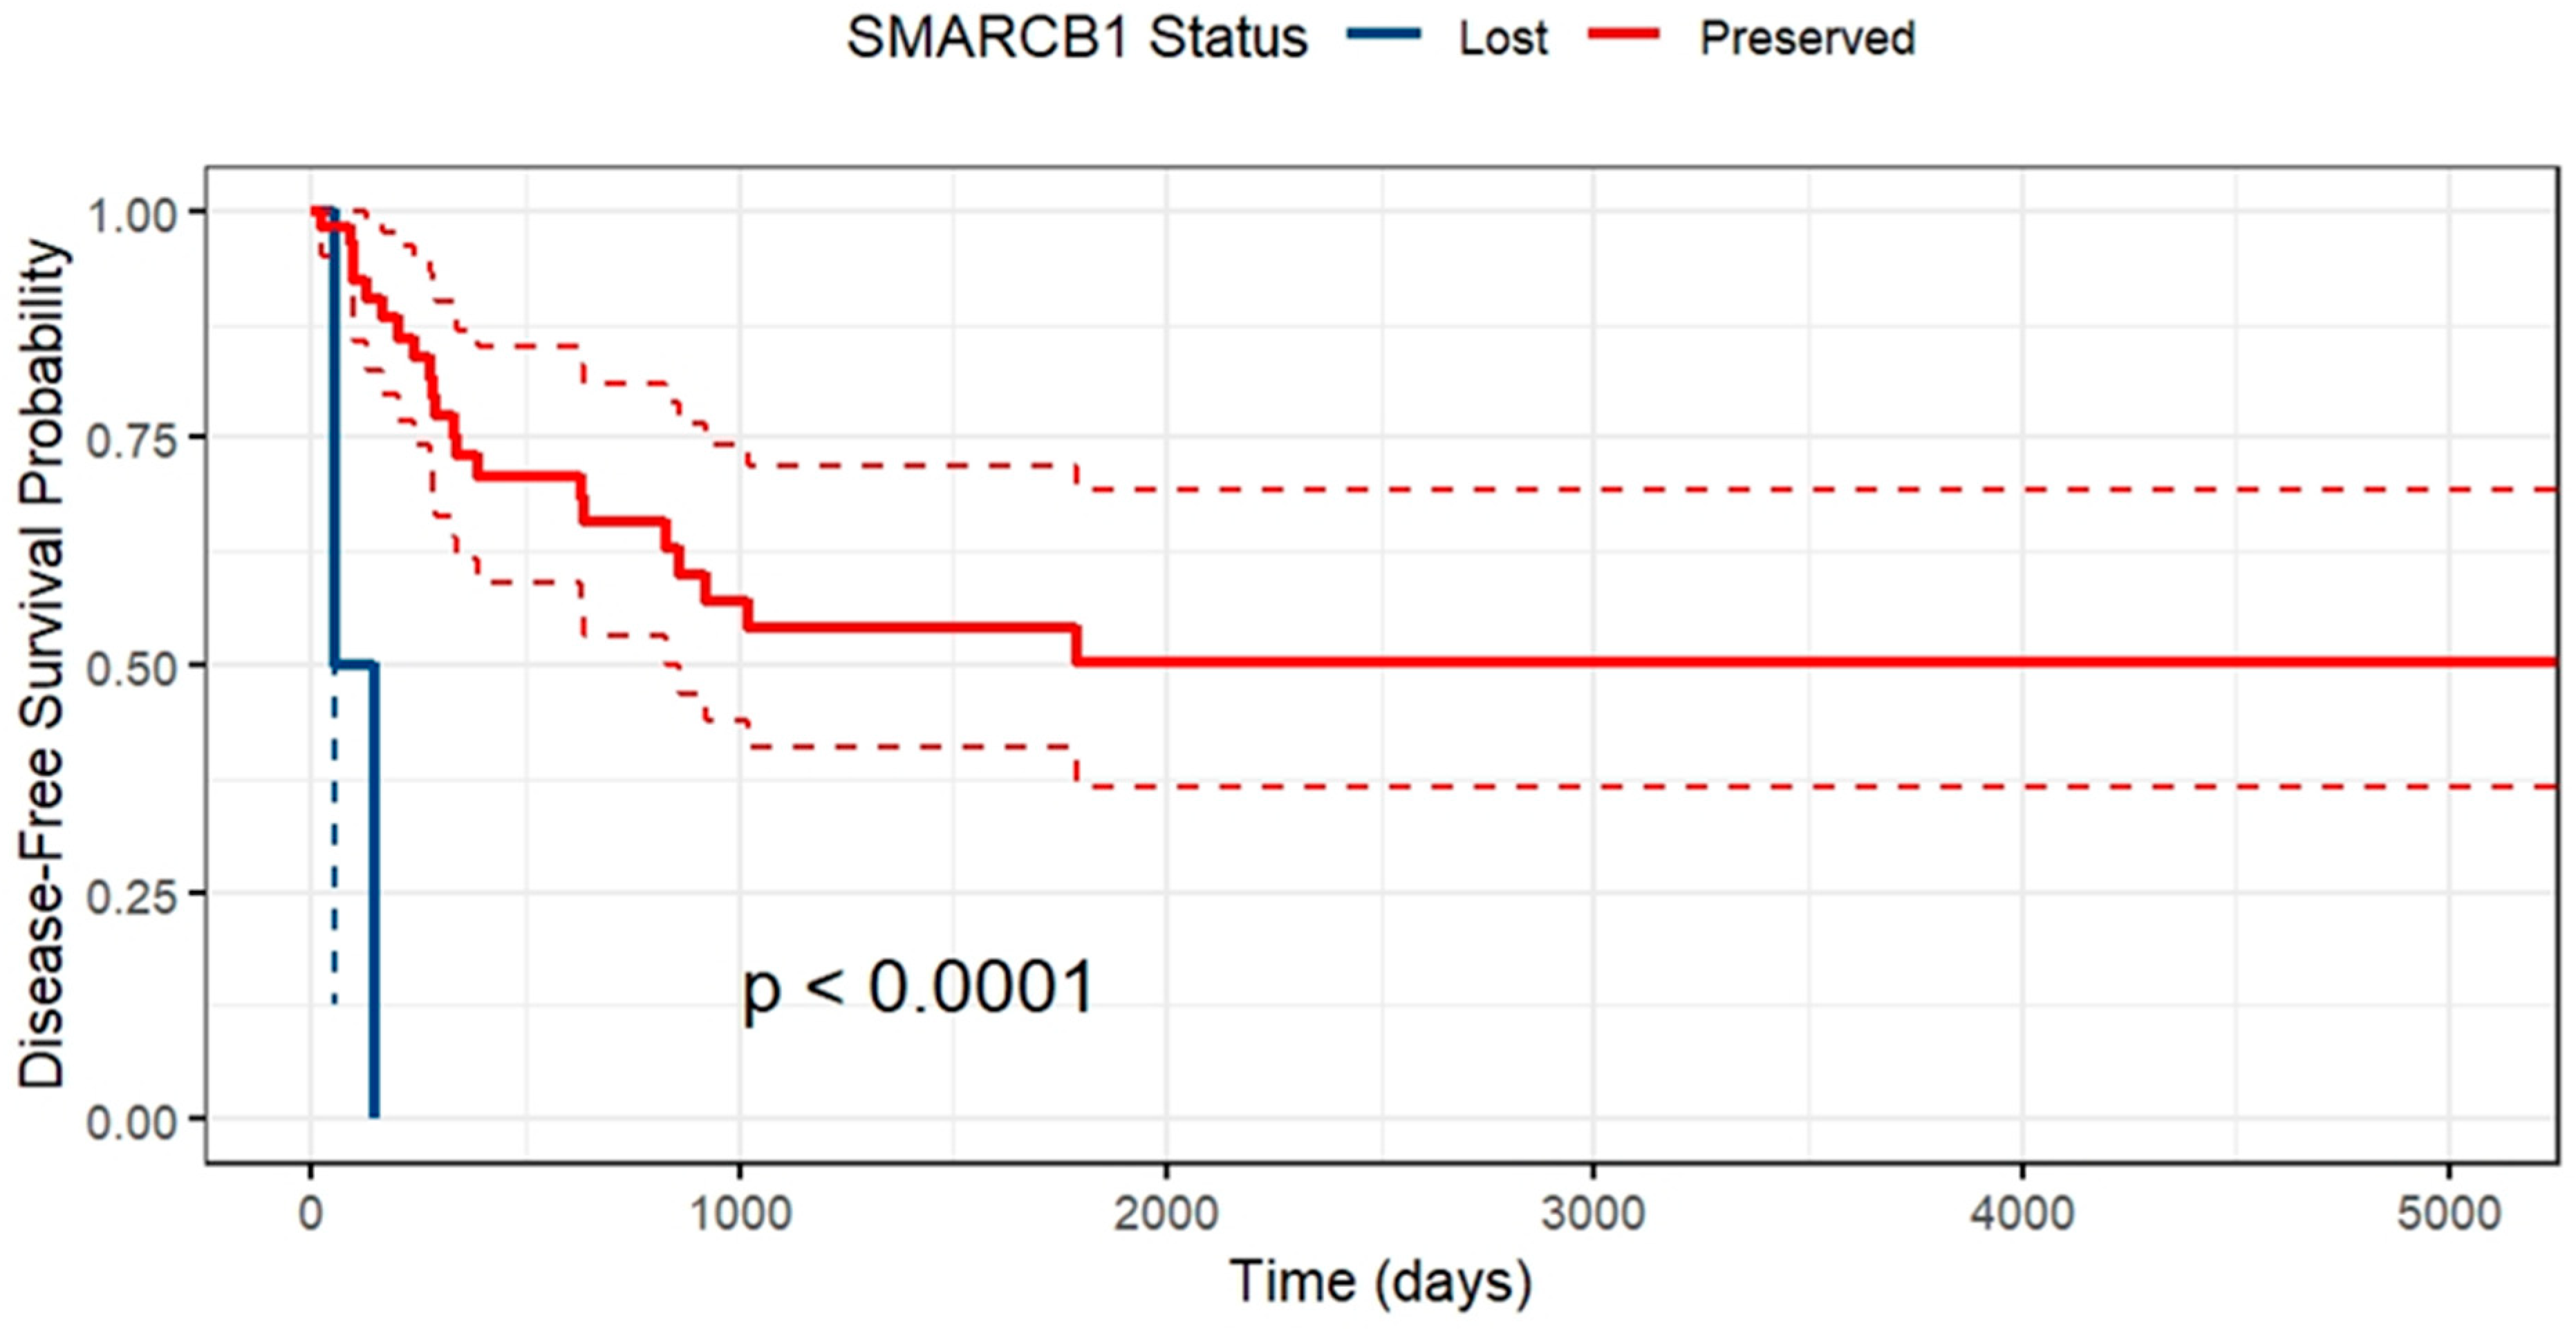

2. Results